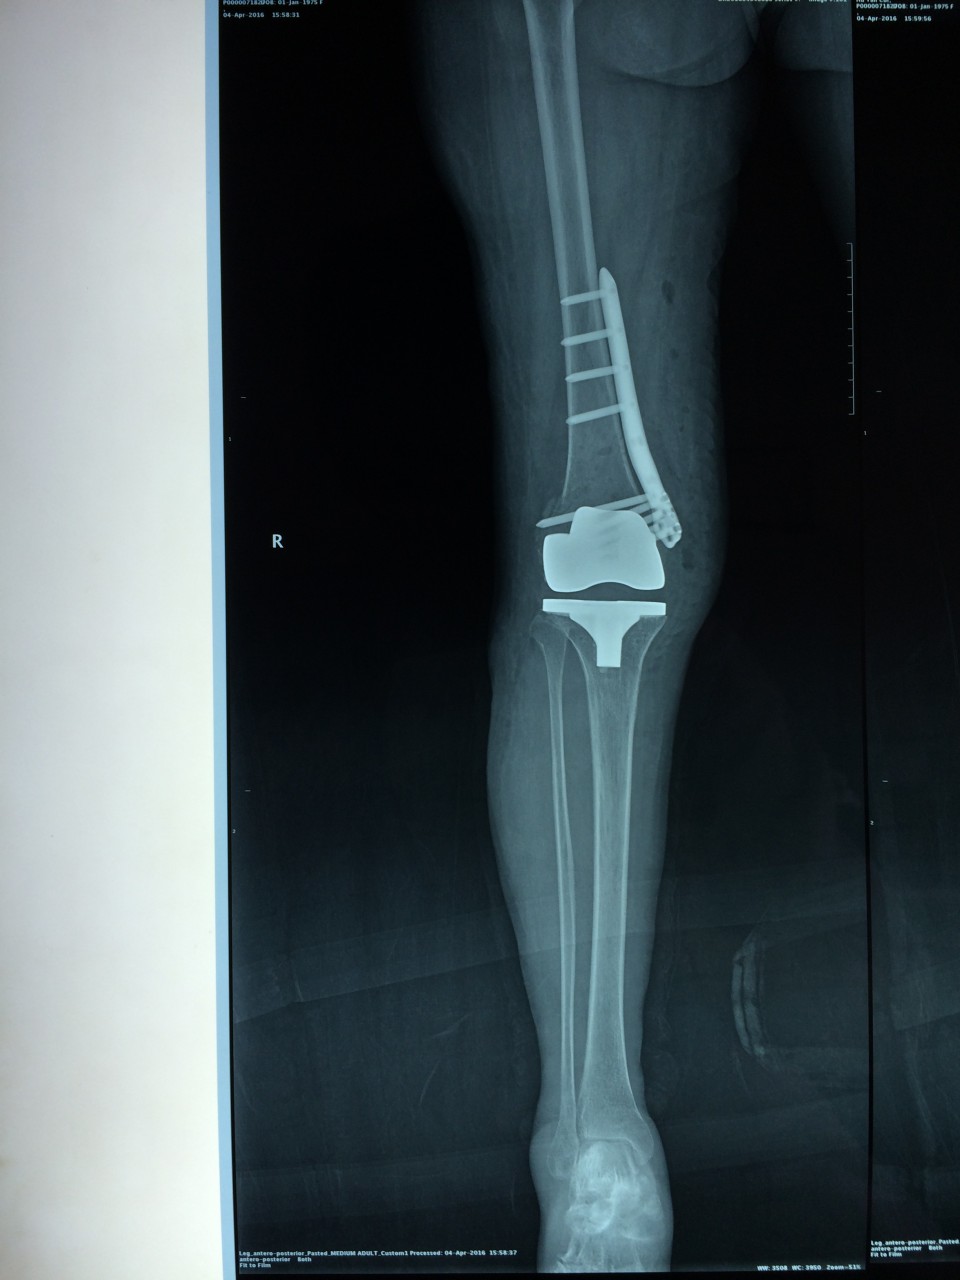

近日,我院关节中心成功完成一例重症类风关合并股骨远端骨折患者的关节置换手术。该患者长期服用激素及免疫抑制剂,骨质疏松较重;受伤前膝关节无法伸直,屈曲畸形,膝关节活动度仅15°;骨折的部位位于股骨远端,骨折处理不当,会直接影响假体的安置,造成手术的失败,因此手术难度非常大,对手术程序及逻辑性的严密度要求高。针对患者的复杂病情及手术难点,关节中心胡勇教授在风湿科、麻醉科的大力配合下,一期完成了骨折固定及人工表面全膝关节置换术。术后患者下肢力线恢复良好,骨折解剖复位,关节恢复过伸,术后5天,关节屈伸活动度恢复致40°。该手术的完成,标志着我院关节中心在复杂性关节病的治疗上又迈出了坚实的一步。